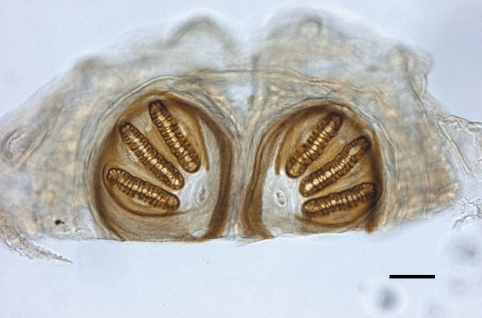

Fig. 1). They were removed endoscopically, and sent to the parasitology laboratory for analysis. Examination of the patient's nose revealed no significant pathologic changes. The larvae were white and 10.8 ± 2.6 mm × 2.0 ± 0.7 mm in size. Examination of posterior spiracles on a glass slide under light microscopy showed that they were in the family Calliphoridae, probably

Lucilia sp., which is endemic in Korea (

Fig. 2). They were fixed in 10% formalin and used for identification. They were identified by Lee In-Yong in Department of Environmental Medical Biology, Yonsei University College of Medicine, as the third instar larvae of

Lucilia sericata. By additional endoscopic examination, no larvae were found from her. She returned from the comatose state, and did not complain any clinical signs of myiasis.

11]. In this case, the identification of the larvae was accomplished mainly by observing the posterior spiracles. It should be needed to rear larvae to adults on small pieces of meat for correct diagnosis, but this was not possible in our case due to the small number of larvae. Because the larvae can reach deep and inaccessible areas of the nose and the paranasal sinuses, the use of nasal endoscope is recommended [

Fig. 2Posterior spiracles of a third-tage larva of Lucilia sericata sampled in the nose of the patient. Bar = 100 µm.